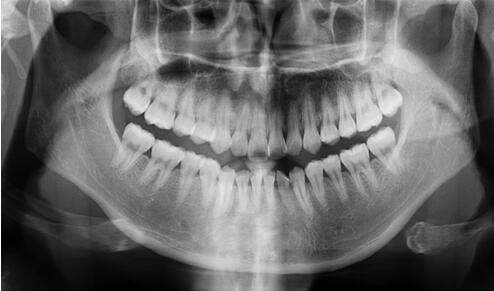

全口曲面斷層片

看似復(fù)雜,用人話說(shuō)就是口腔牙齒的X光片。

牙醫(yī)通過(guò)對(duì)這張片的分析,能找出潛藏的牙周疾病問(wèn)題、牙根發(fā)育等情況。通常是否拔牙、拔哪個(gè)牙、怎么拔,就是靠它了!